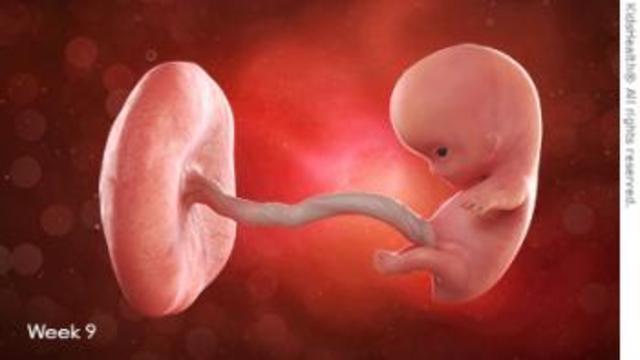

• Semana 9

Semana 9

Se forman los pezones y los folículos pilosos.

Los brazos crecen y se desarrollan los codos.

Se pueden observar los dedos del pie del bebé.

Todos los órganos esenciales del bebé han comenzado a crecer.